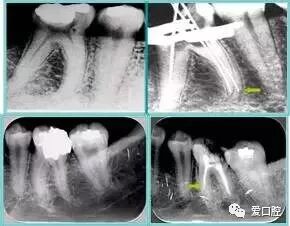

常见有修复性钙化和增龄性钙化。下面为根管钙化 X 线片。

牙胶尖什么颜色最全整理 | 根管治疗标准步骤和细节把握_https://www.jmylbn.com_新闻资讯_第35张

右图及下图为器械折断的 X 线片。箭头处示折断器械

牙胶尖什么颜色最全整理 | 根管治疗标准步骤和细节把握_https://www.jmylbn.com_新闻资讯_第36张